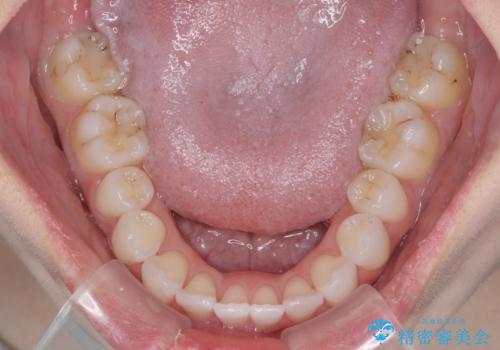

治療開始から4ヶ月ほどで概ね歯列が整い、その後の3ヶ月で細かい部分を仕上げていきました。

短期間で綺麗に仕上がり、患者様には大変満足していただきました。